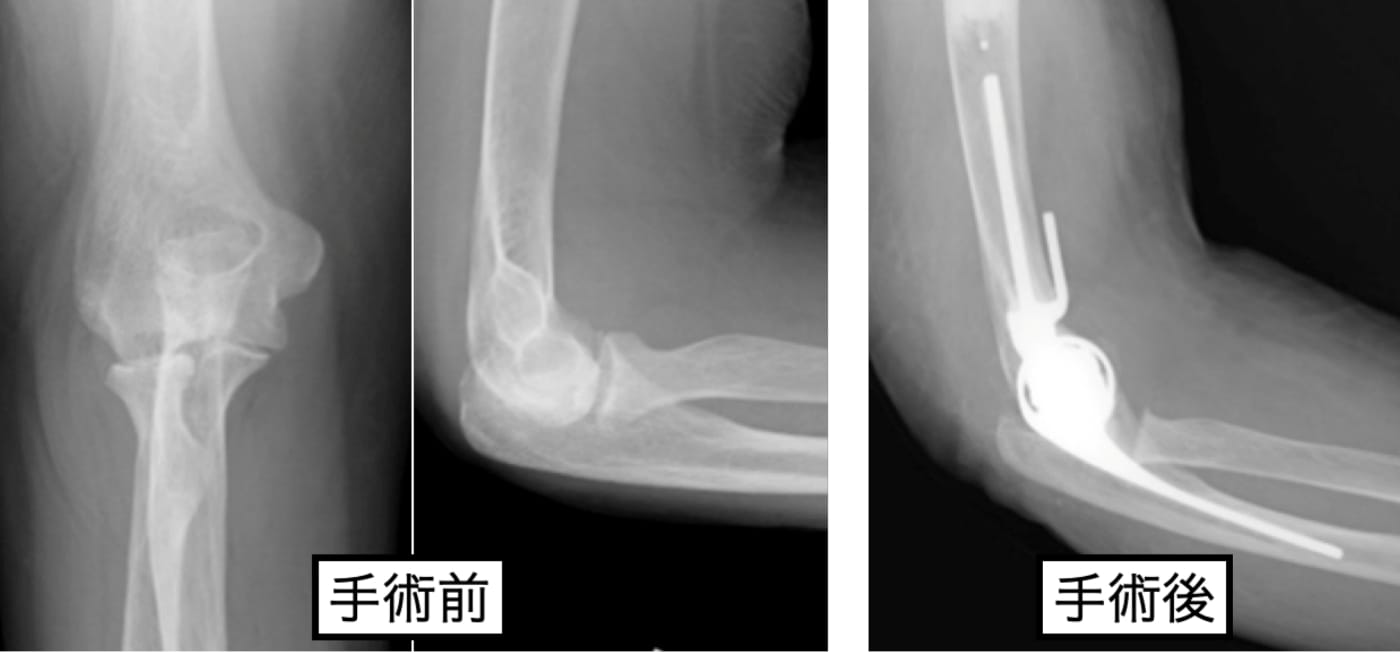

リウマチによる肘部変形

適応あれば、人工関節を用いた再建術を行っています。術後は上肢のリハビリテーションに特化したハンドセラピストによる後療法を行っています。